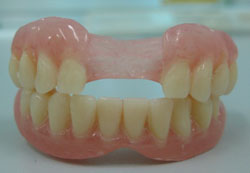

Điều trị răng có hai giải pháp: làm hàm giả hoặc cắm Implant.

Làm hàm giả tháo lắp cho trẻ. Gắn răng, hướng dẫn trẻ cách bảo quản và sử dụng

Gắn răng, hướng dẫn trẻ các bảo quản và sử dụng

Nhờ hàm giả mới này, khuôn mặt của trẻ thay đổi về mặt thẫm mỹ, giúp trẻ ăn nhai tốt hơn, trẻ tự tin trong giao tiếp và vui sống trong xã hội.

Bệnh nhân sẽ được tái khám mỗi 6 tháng để đánh giá sự phát triển của xương hàm, khi có sự không thích ứng giữa hàm giả cũ và xương hàm của trẻ, Bác sĩ sẽ làm lại hàm giả mới cho bé. Theo dõi liên tục cho tới khi xương hàm phát triển ổn định vào khoảng 19-25 tuổi, ta sẽ không phải thay hàm giả nữa.